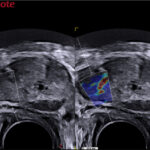

- elaXto funkcija, kuri leidžia atlikti kiekybinius audinių elastografijos tyrimus

- QElaXto funkcijos pagalba atliekami kokybiniai audinių elastografijos tyrimai

- Fusion imaging funkcijos pagalba sinchronizuojami dviejų diagnostinių įrankių (MRT, KT, PET, radiografijos, mamografijos) 2D arba 3D vaizdai